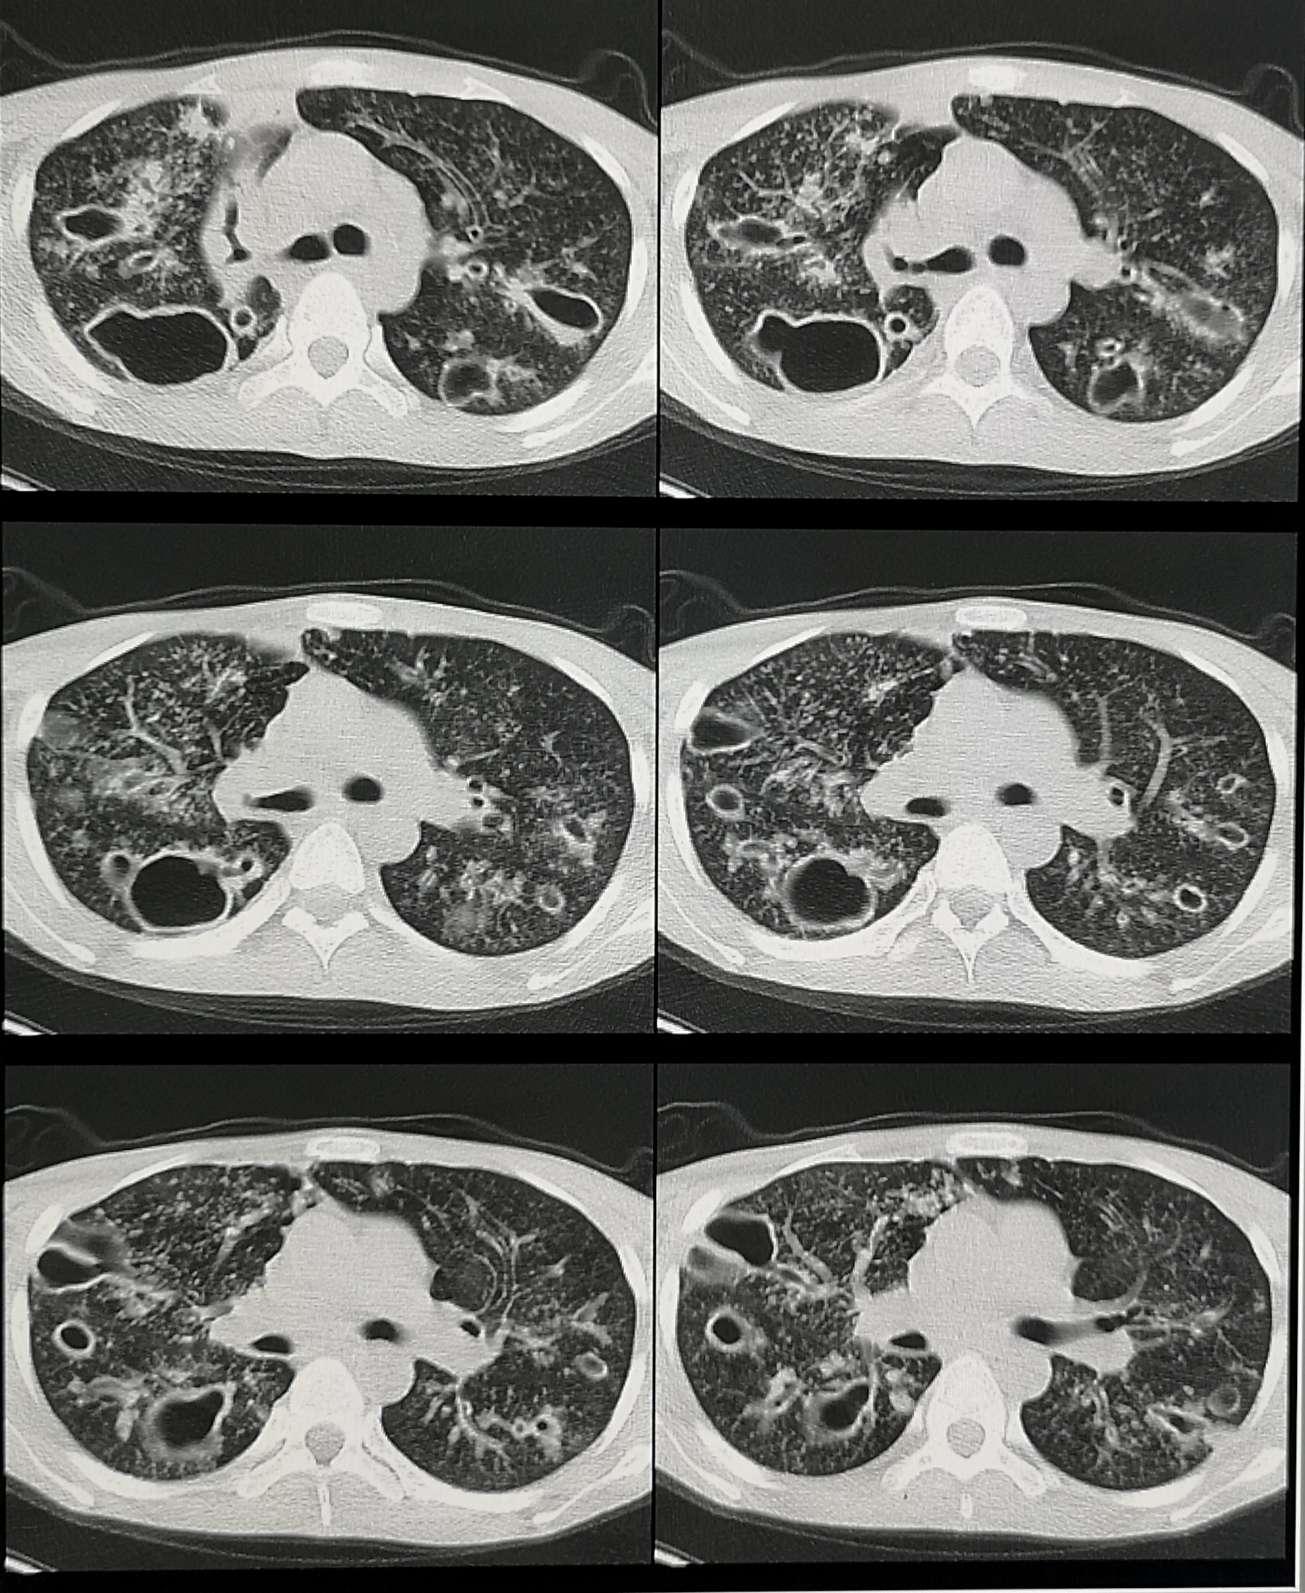

于是我们给小伙子加做了胸部CT:

果然是典型的活动性肺结核:双肺多发树芽征、磨玻璃影,大小不等的空洞、支气管扩张,肺实变。